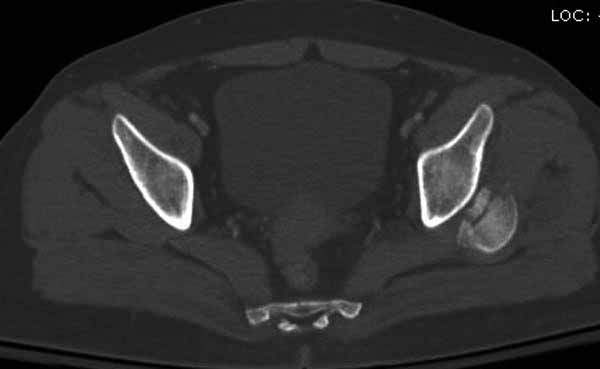

Женщина 28 лет, политравма.

По протоколу обследования больных с травмой сделаны все исследования и выставлен диагноз: разрыв печени и селезенки; множественные переломы ребер и лицевого черепа; стабильный перелом позвоночника, переломо-вывих головки левого бедра, перелом диафиза правого бедра, переломо-вывих правого тарана.

----------- следущая часть -----------

Вложение не в текстовом формате было извлечено&hellip;

Имя     : 9 CT4.JPG

Тип     : image/jpg

Размер  : 25067 байтов

Описание: отсутствует

Url     : http://weborto.net:8080/pipermail/ortho/attachments/20120618/4c283bf6/attachment-0023.jpg